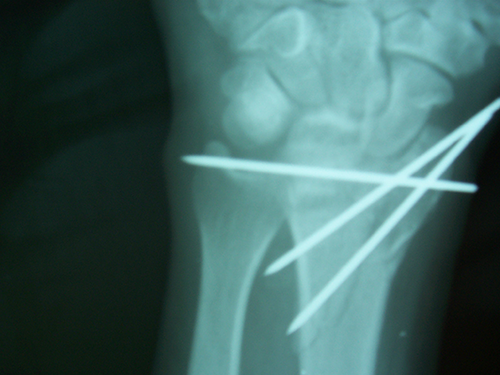

Case:4 Comminuted Intra – Articular Lower End Fracture Radius

A patient, aged 46 years following vehicular accident came with swollen painful wrist & hand. He had been diagnosed to have closed comminuted fracture lower end of right Radius. He was treated operatively with closed reduction & ‘K’ wiring under regional Anaesthesia.

Pre-Op

Pre-op Lateral

Post-op AP

One and Half Months Follow-Up